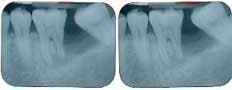

This patient presented with a missing No. 18 and hopeless No. 17 and No. 19 due to localized severe periodontal disease, recurring abscesses, and tooth migration. Severe bone loss can be seen on the initial periapical (Fig. 1) and panoramic (Fig. 2) radiographs.

Fig. 1